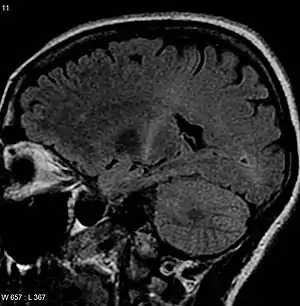

The defining feature of ALS is the death of both upper motor neurons (located in the motor cortex of the brain) and lower motor neurons (located in the brainstem and spinal cord).[79] In ALS with frontotemporal dementia, neurons throughout the frontal and temporal lobes of the brain die as well.[35] The pathological hallmark of ALS is the presence of inclusion bodies (abnormal aggregations of protein) in the cytoplasm of motor neurons. In about 97% of people with ALS, the main component of the inclusion bodies is TDP-43 protein;[10] however, in those with SOD1 or FUS mutations, the main component is SOD1 protein or FUS protein, respectively.[27] The gross pathology of ALS, which are features of the disease that can be seen with the naked eye, include skeletal muscle atrophy, motor cortex atrophy, sclerosis of the corticospinal and corticobulbar tracts, thinning of the hypoglossal nerves (which control the tongue), and thinning of the anterior roots of the spinal cord.[10] Aside from the death of motor neurons, two other characteristics common to most ALS variants are focal initial pathology, meaning that symptoms start in a single spinal cord region, and progressive continuous spread, meaning that symptoms spread to additional regions over time. Prion-like propagation of misfolded proteins from cell to cell may explain why ALS starts in one area and spreads to others.[27]

Because symptoms of ALS can be similar to those of a wide variety of other, more treatable diseases or disorders, appropriate tests must be conducted to exclude the possibility of other conditions.[4] One of these tests is electromyography (EMG), a special recording technique that detects electrical activity in muscles.[4] Certain EMG findings can support the diagnosis of ALS.[4] Another common test measures nerve conduction velocity (NCV).[4] Specific abnormalities in the NCV results may suggest, for example, that the person has a form of peripheral neuropathy (damage to peripheral nerves) or myopathy (muscle disease) rather than ALS. While a magnetic resonance imaging (MRI) is often normal in people with early stage ALS, it can reveal evidence of other problems that may be causing the symptoms, such as a spinal cord tumor, multiple sclerosis, a herniated disk in the neck, syringomyelia, or cervical spondylosis.[4]